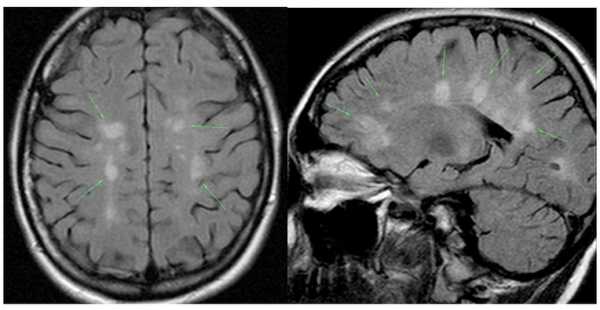

Зелеными стрелочками показаны очаги рассеянного склероза на МРТ